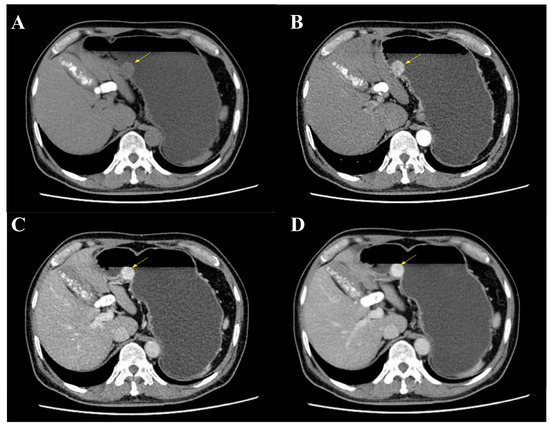

The mass was also revealed during an abdominal and pelvic enhanced computer tomography (CT), with a soft tissue density and a clear boundary (Figure 2A). It showed a significant enhancement during the arterial phase, portal venous phase and delayed phase (Figure 2B–D). A significantly increased enhancement of the mass was found during the portal venous phase, with a CT value of 156HU, and a glomangioma was suspected. With the exception of multiple gallstones, no lymph nodes or other abnormal phenomenon were found.

Figure 2. Abdominal and pelvic enhanced CT. (A) CT showed a mass at the gastric body with a clear boundary and soft tissue density (yellow arrow). (B) The mass was enhanced during arterial phase (yellow arrow). (C) An increased enhancement of the mass was found during portal venous phase with a maximum CT value of 156HU (yellow arrow). (D) The mass was still enhanced during delayed phase (yellow arrow).